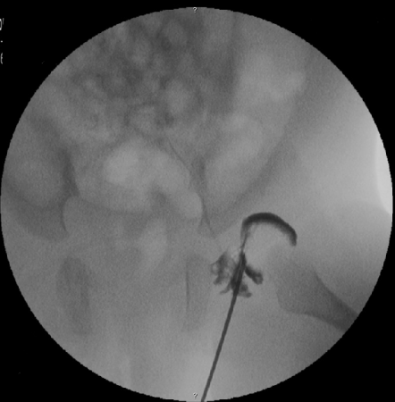

• Μετά την ηλικία των 6 μηνών διενεργείται  κλειστή ανάταξη μετά από αρθρογραφία στο χειρουργείο υπό γενική αναισθησία και τοποθέτηση γύψου. Σε ορισμένες περιπτώσεις συνδυαστικά με την κλειστή ανάταξη, διενεργείται διάνοιξη ισχίου με έσω προσπέλαση με μικρή τομή στους προσαγωγούς του ισχίου

Η εικόνα απεικονίζει την διενέργεια αρθρογραφίας από περιστατικό του Δρ. Ζένιου.  Η εξέταση αυτή βοηθάει αρκετά στον προ-εγχειρητικό σχεδιασμό πριν από την ανάταξη  ισχίου.